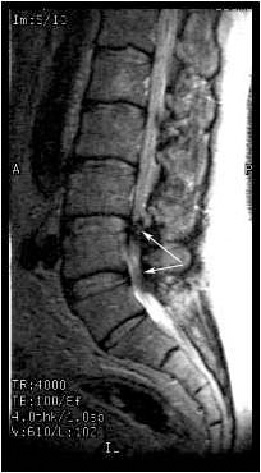

Стенозом позвоночного канала называют уменьшение его размера в передне-заднем направлении, а также уменьшение его ширины. Сужение позвоночного канала в поясничном отделе наиболее часто встречается при гипертрофии (увеличении) фасеточных суставов, желтой связки, уменьшении фораминального отверстия (места выхода нервного корешка из позвоночного канала) за счет разрастания остеофитов, изменении оси позвоночника (сколиоз, спондилолистез). (Рис.1,2А,В)